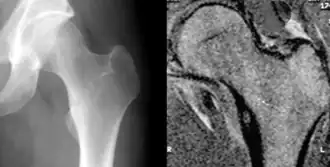

Les radiographies de l'ostéome ostéoïde montrent généralement une clarté ronde, contenant un nidus central sclérotique dense (la lésion caractéristique de ce type de tumeur) entouré d'os sclérotique. Le nidus est rarement plus grand que 1,5 cm.[réf. nécessaire]

La lésion peut dans la plupart des cas être détectée au scanner, à la scintigraphie osseuse et à l'angiographie.

L'IRM n'ajoute que peu aux résultats.

La tomodensitométrie est utile pour la localisation. Le balayage des radionucléides montre une absorption intense qui permet la localisation à l'aide d'un détecteur portatif lors d'une intervention chirurgicale et permet de confirmer que la totalité de la lésion a été retirée[3],[4].